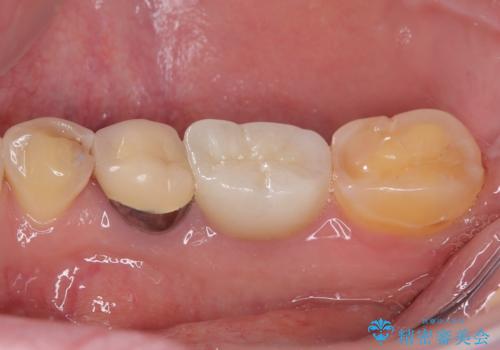

検診で見つかった齲蝕のセラミックインレー修復

- 検診で初期の齲蝕が見つかった患者様です。

これ以上神経の治療や被せものになりたくないため、初期のうちにしっかりとした治療をしたいとのことでした。

齲蝕をしっかりと除去して、精度の高いシリコーンによる型どりを行いセラミックインレーで修復しました。

唾液による接着阻害を防ぐために、ラバーダム防湿を行っています。

精度の高い治療は再度齲蝕になるリスクが低いです。